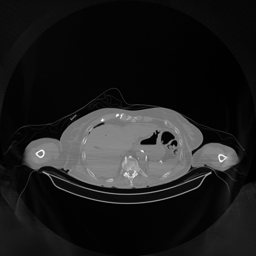

The results for simulated noisy data are shown in Fig. 2. The first and third rows display two representative slices from the test set, and the second and fourth rows present the corresponding error maps. The traditional WCE method suppresses cupping artifacts and recovers some missing anatomical structures but still shows noticeable deviations from the ground truth. Predictions from the four diffusion-based models demonstrate a markedly improved ability to restore anatomical structures. Among them, cDDPM fails to fully reconstruct the patient bed and retains residual noise in its outputs. This noise is attributable to an incomplete reverse denoising process rather than residual Poisson noise, as evidenced in our noise-free experiments (Fig. 5 in the Appendix). PatchDiffusion, diffusionGAN, and I2SB achieve similar visual quality, with I2SB producing the cleanest and most consistent reconstructions.

The experimental results on clinical head data are shown in Fig. 4. The reference images were reconstructed using the fast iterative shrinkage-thresholding algorithm (FISTA) with total variation regularization from non-truncated projection data. In the WCE reconstructions (Fig. 4(b)), severe truncation prevents accurate recovery of anatomical structures outside the FOV. Despite being trained solely on simulated data with a domain gap, all deep learning models can restore a substantial portion of the missing anatomy. Among them, the diffusion-based methods recover soft-tissue boundaries more faithfully than the conventional deep learning approach FBPConvNet, highlighting their stronger image generation capability. However, cDDPM reconstructions exhibit more noticeable noise than those from other methods, consistent with the simulated data results. The patchDiffusion model introduces artifacts within the FOV, likely due to its patch-wise processing strategy. While I2SB shares the same limitations as other diffusion models in perfectly restoring soft-tissue detail, it produces fewer residual noise patterns and fewer artifacts within the FOV boundaries. Overall, Fig. 4 demonstrates the strong efficacy of I2SB in reconstructing real CBCT data.